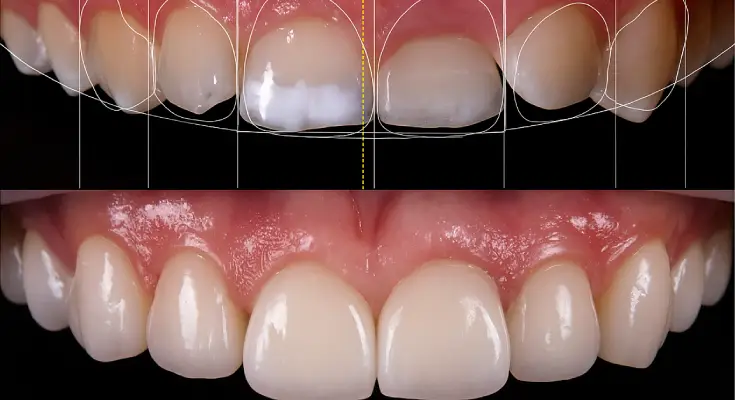

Digital Smile Design (DSD) Software: Fast-Tracking Your Smile Transformation

DSD or Digital Smile Design software aids dentists in creating unique smile designs. It lets them generate many treatment plans and allows patients to view the results beforehand. This way, patients have control over the final results, and dentists can also have their say.

Benefits of Digital Smile Design for Patients in NYC

- Saves time on making and remaking the smile design

- Patients can see the results before starting

- Result previews work to build trust between the dentist and patients

- 3D planning gives dentists a detailed treatment plan to follow

- This imagery will give dentists more insight into the necessary procedures

Using this software saves time and can improve the accuracy of the treatment plan. This brings you closer to your dream smile, faster!